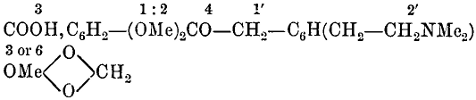

| Williams’ Apparatus for Investigating Action of Poisons on the Frog’s Heart, | 44 | |